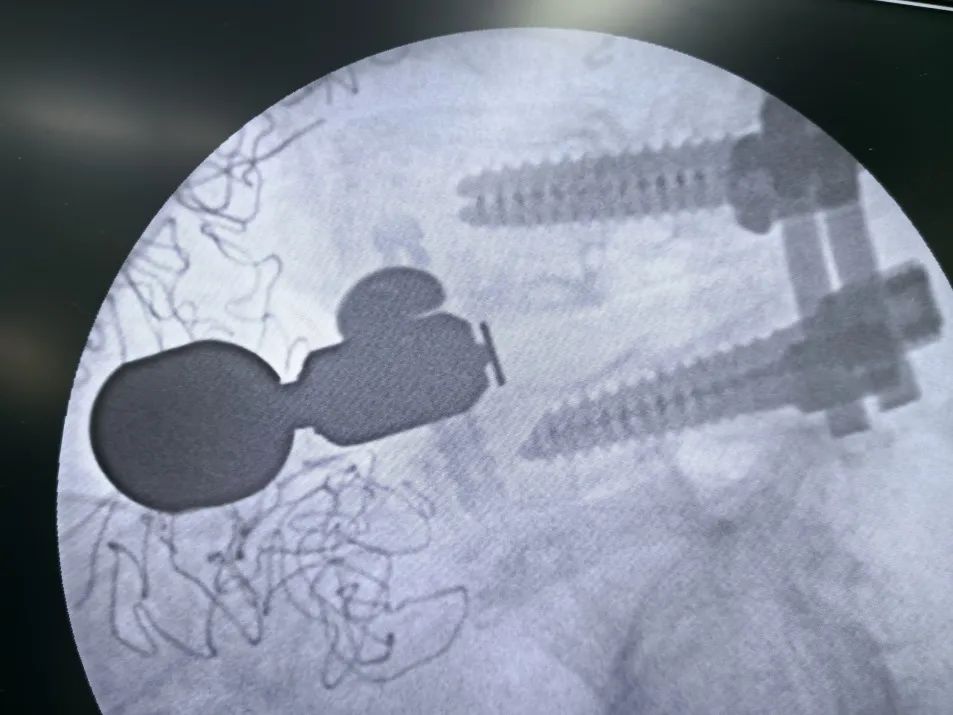

正視圖:頭尾側(cè)固定夾均已完全打入

最終透視